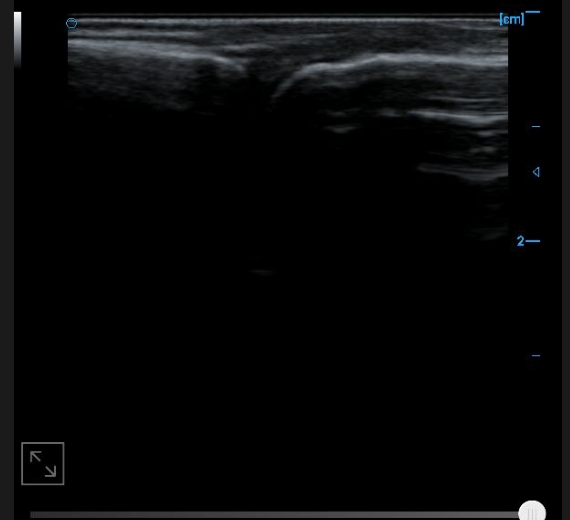

Patellar tendon B image